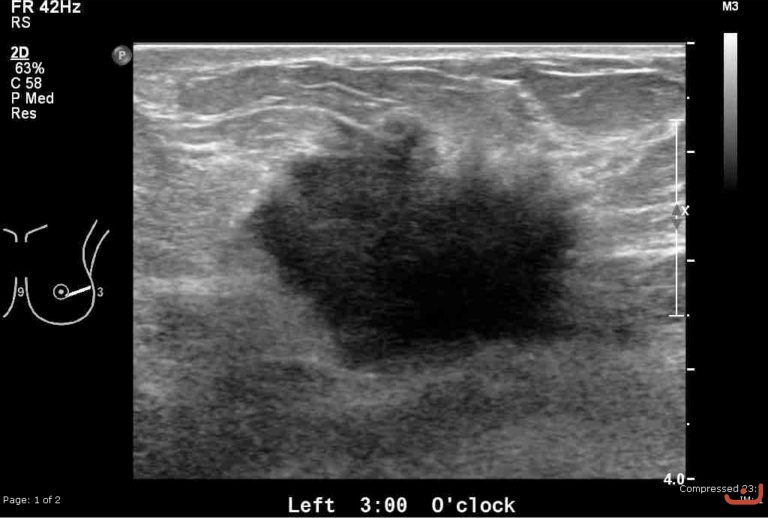

Malignant solid mass

Date

Thursday, 30 April 2015

173.08 KB (768 x 518 px)